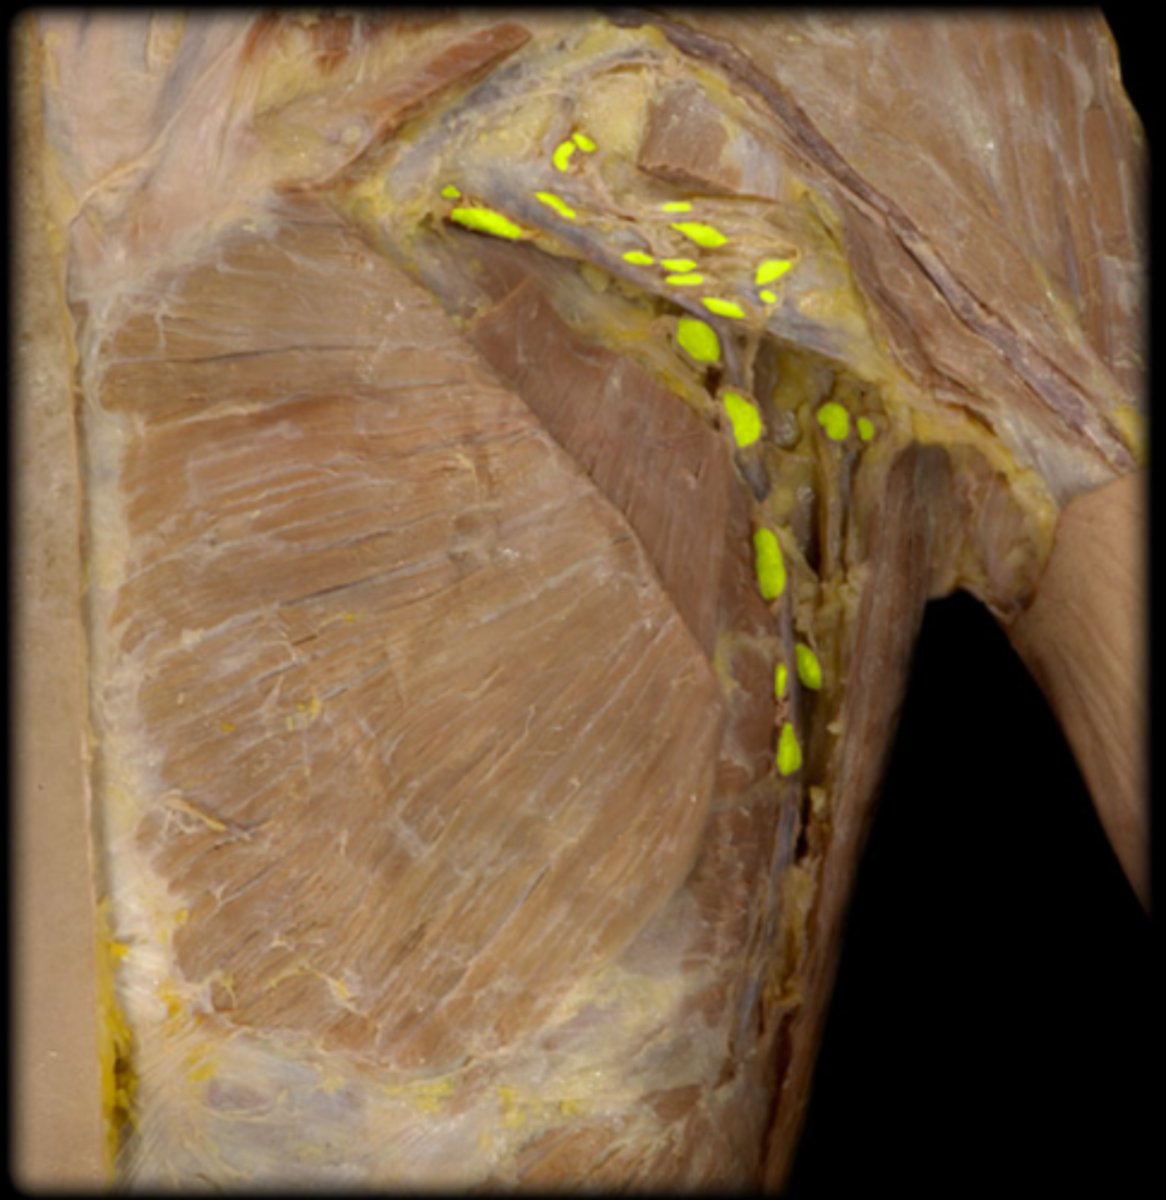

axillary lymph nodes